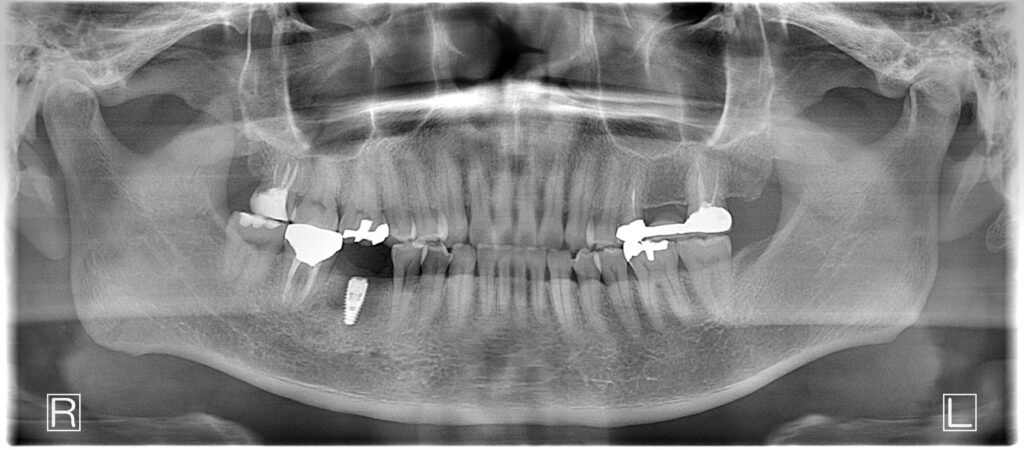

今日のインプラントオペは下顎右側6番のケースです。歯根破折したケースでしたので頬側の骨がなくGBR併用。初期固定も良かったが、骨補填材を入れているので2回法にしました。

特に問題なく終了。